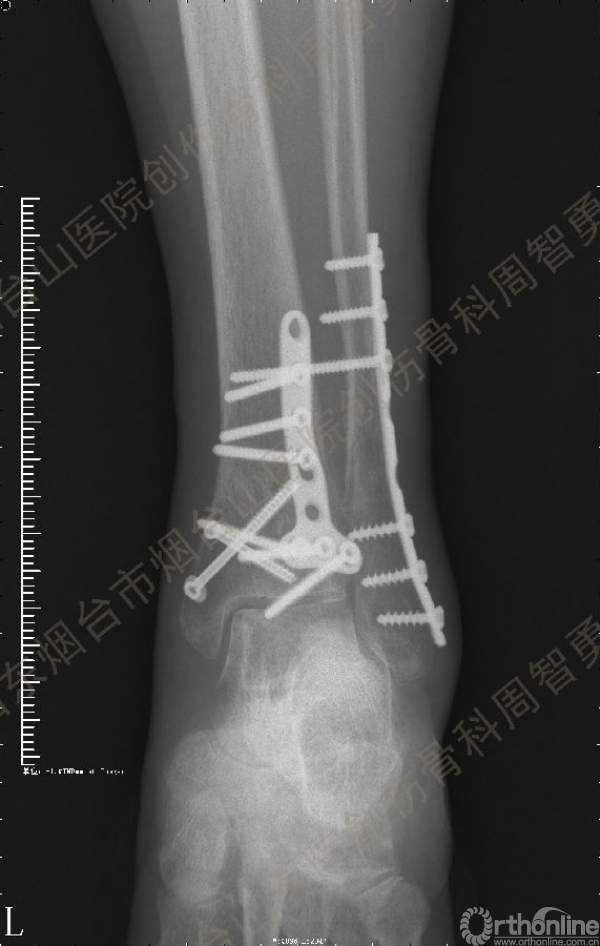

患者取俯卧位,轻度屈膝,小腿下垫枕使足离开床面。取长约10cm的踝关节后外侧切口,皮肤切口位于外踝后缘与跟腱的中线,远侧延伸至外踝尖。皮下与深筋膜间显露、保护小隐静脉和腓肠神经,纵向切开腓骨肌浅面深筋膜,显露腓骨肌腱。将腓骨肌腱牵向外侧显露后浅室和后深室间隔,透过肌间隔可见踇长屈肌。切开肌间隔显露踇长屈肌并向内侧牵开,显露胫骨远端后侧骨折块。保护腓动脉、下胫腓后韧带和骨折块上的骨膜。在后内侧骨折块和后外侧骨折块中间的骨折线切开骨膜并骨膜下游离数毫米,分别以胫后肌腱腱鞘和下胫腓后韧带为铰链,将后内侧骨折块和后外侧骨折块翻向内侧和外侧。显露后内侧骨折块腹侧向近端塌陷的骨软骨骨折块。见后内侧骨折块腹侧有约4.0 mm×3.0 mm×3.0 mm大小向近端塌陷的骨软骨骨折块,给予切除。取长约5cm的踝关节后内侧入路,切开皮肤皮下并适当向两侧游离,不切开屈肌支持带,仅切开后内侧骨折块内侧缘和近侧缘的骨膜。通过后外侧入路和后内侧入路显露后内侧骨折块的外侧缘、近侧缘和内侧缘,直视下解剖复位后,2.0 mm克氏针临时固定。直视下解剖复位后外侧骨折块,并用2.0 mm克氏针临时固定。返回后外侧切口,向外侧游离皮瓣,内牵腓骨长短肌腱显露外踝骨折,解剖复位后用2.0 mm克氏针临时固定。术中透视显示骨折块解剖复位。一枚4.0mm空心螺钉固定于后内侧骨折块的内上缘,另一枚4.0mm空心螺钉固定于后丘,5孔桡骨远端T型接骨板抗滑固定于后内侧骨折块和后外侧骨折块。8孔1/3管状板固定外踝骨折。术中Cotton试验阳性,复位下胫腓联合后,1枚3.5mm皮质骨螺钉固定。Chaput骨折块未作处理。术中及术后X线摄片示骨折解剖复位,内固定物位置正确。术后,踝关节于背伸0~5°,短腿石膏后托或支具固定2周。2周去除外固定开始踝关节主动功能练习。术后8周,X线片示骨折解剖复位,骨折线模糊,内固定物在位(图3a,b)。术后第11周开始部分负重,第13周拔除固定下胫腓联合的螺丝钉,逐步开始完全负重。术后4个月复查:X线片示骨折解剖复位,骨折线消失,内固定物在位;左侧踝关节主动背伸较健侧差10°,跖屈差10°;踝关节无疼痛,肌力较健侧无明显减退。

↑ 图 3a

图 3 术后8周X线片示骨折解剖复位,骨折线模糊,内固定物在位